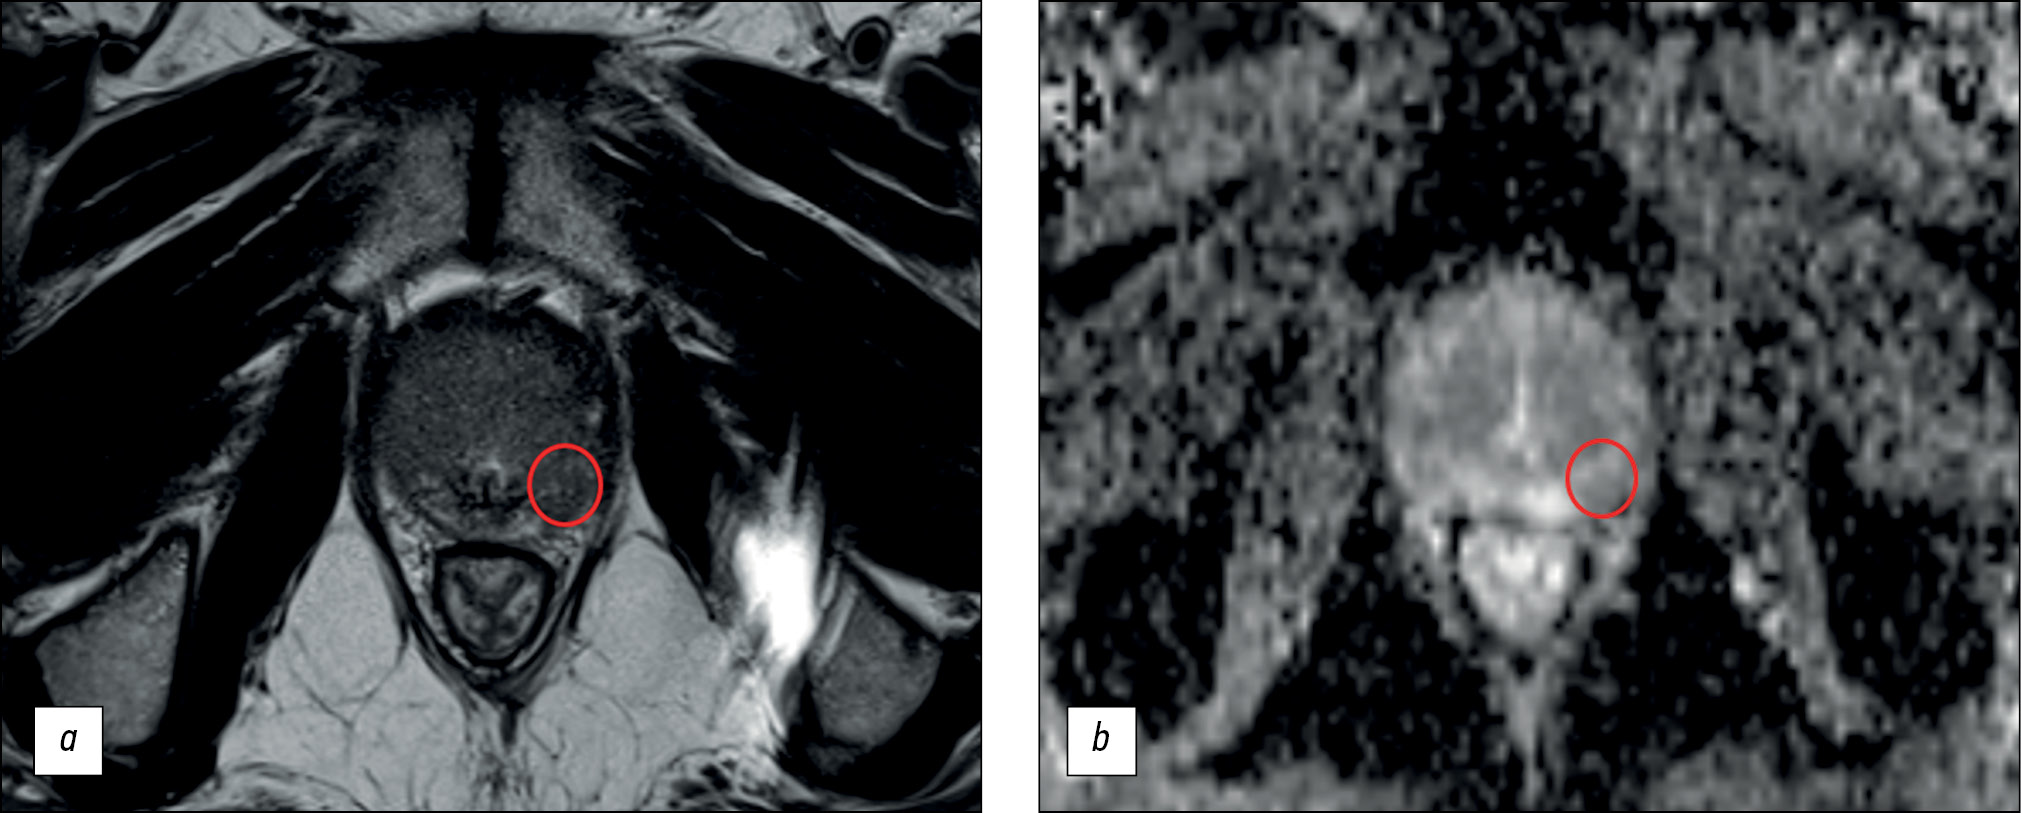

BACKGROUND: Magnetic resonance imaging can detect clinically significant prostate cancer and diagnose extracapsular extension and cancer stage. A scanning protocol that includes only T2-weighted and diffusion-weighted images represents a viable alternative to multiparametric magnetic resonance imaging provided that the high diagnostic accuracy of the test is maintained. In recent studies, biparametric and multiparametric magnetic resonance imaging demonstrated slight differences in the diagnostic accuracy in detecting prostate cancer.

AIM: To compare the diagnostic accuracy of biparametric and multiparametric magnetic resonance imaging for the detection of clinically significant prostate cancer using PI-RADS v2.1 with magnetic resonance imaging-guided multifocal biopsy as the gold standard.

MATERIALS AND METHODS: This retrospective study initially processed the medical records of 126 patients. The inclusion criteria were as follows: presence of PI-RADS 2.1 multiparametric magnetic resonance imaging, clinical information on free and bound prostate-specific antigen blood levels, a multifocal prostate biopsy performed, and a time interval between magnetic resonance imaging and biopsy of no more than 14 days. Three investigators (radiologists with <2, 2–5, and >5 years of experience) independently evaluated biparametric magnetic resonance imaging of the prostate for the presence of pathological foci. After 2 weeks, the researchers evaluated the multiparametric magnetic resonance imaging dataset of the prostate. Each lesion detected, starting from PI-RADS category 3, was compared with the result of a multifocal fusion biopsy. The biopsy result was presented as a sum of Gleason scores, and a Gleason score of ≥7 was considered clinically relevant. According to magnetic resonance imaging data, findings meeting PI-RADS criteria 4 and 5 were considered tumor foci.